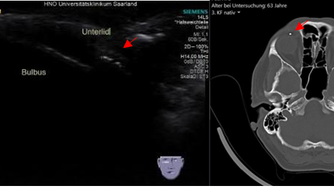

Die Sonografie dient der Ausdehnungsbestimmung (Staging) von tumorösen Veränderungen der Kopf-Hals-Region. Vor- und nach Behandlungen werden besonders die Halslymphknoten untersucht, ob sich tumorverdächtige bildmorphologische Veränderungen zeigen.

Bei Entzündungen oder Verletzungen der Gesichtsweichteile hilft die Sonografie, unter Vermeidung von Röntgenstrahlen eine Diagnose zu sichern.